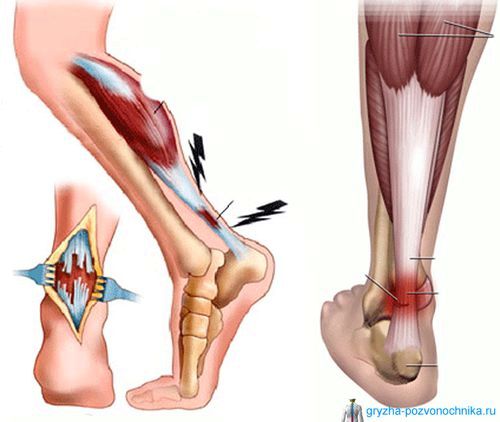

Розрив зв'язок гомілкостопу ^

Супроводжується сильними набряками, а також «синдромом шухляди». Для того щоб його перевірити однією рукою міцно охоплюють гомілку, а, інший, намагаються зрушити стопу. Якщо вона легко ковзає вперед-назад, значить зв'язки розірвані.

Розрив зв'язок гомілкостопу